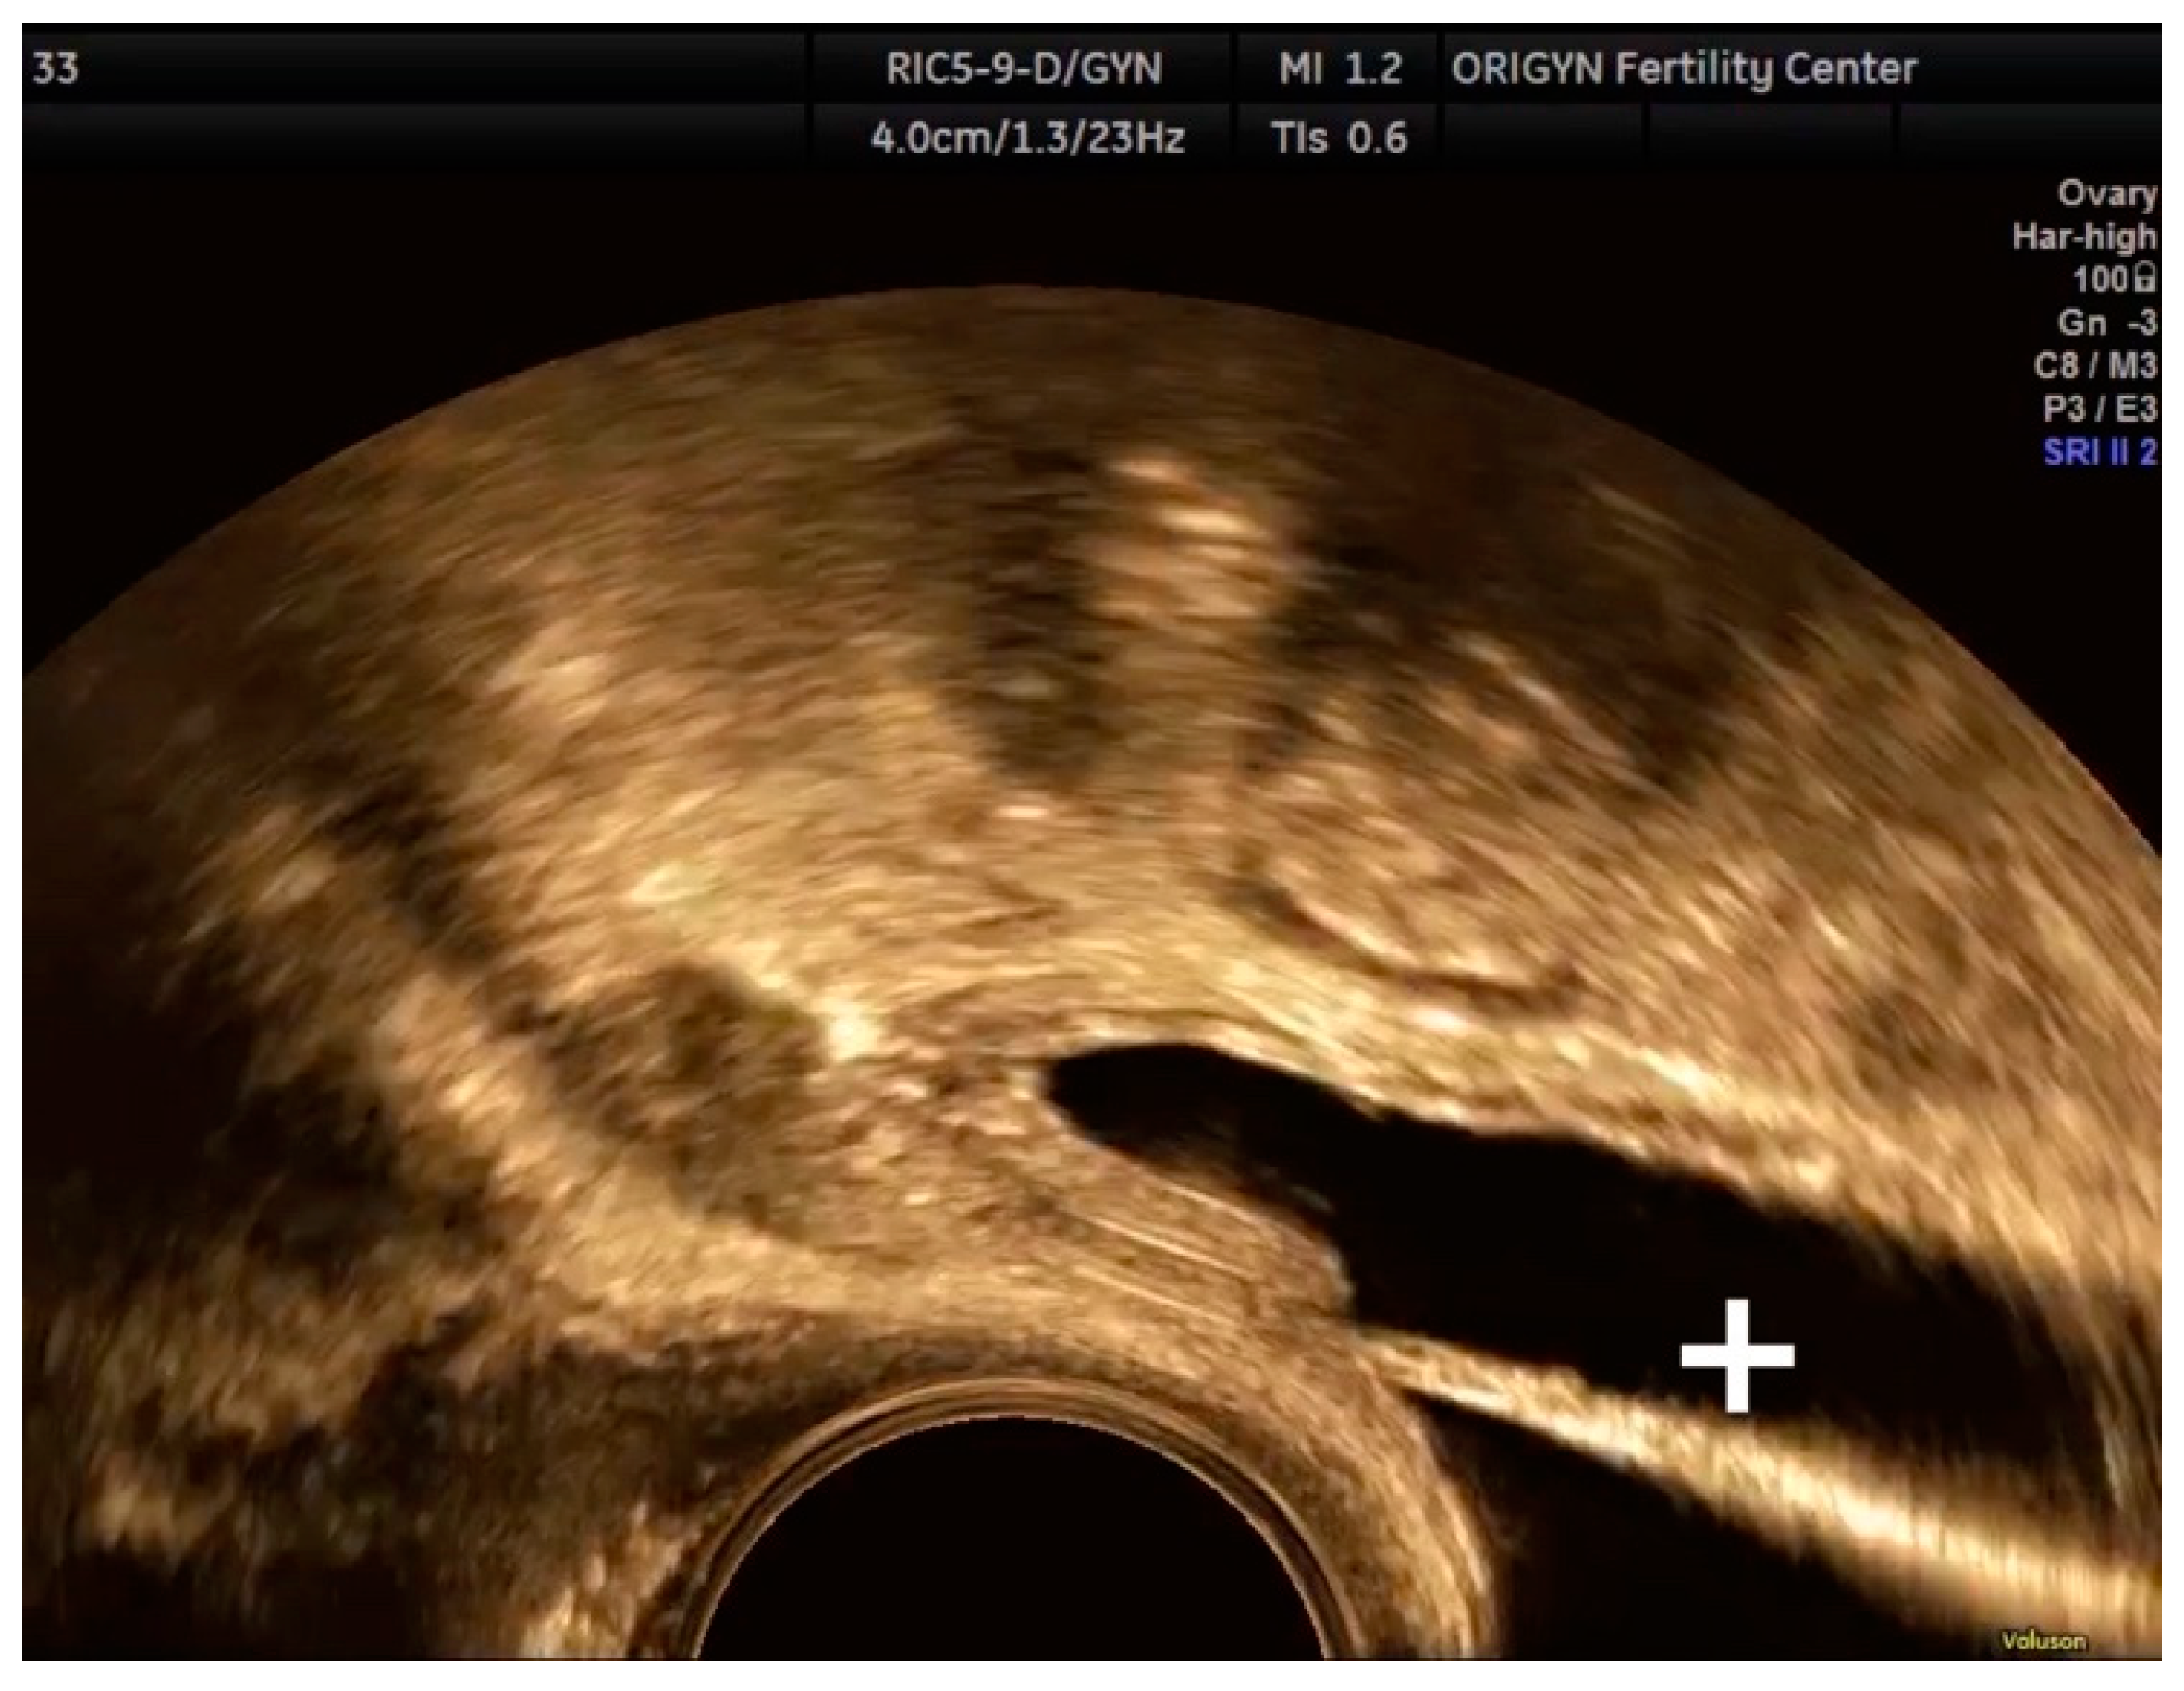

4. Conclusions